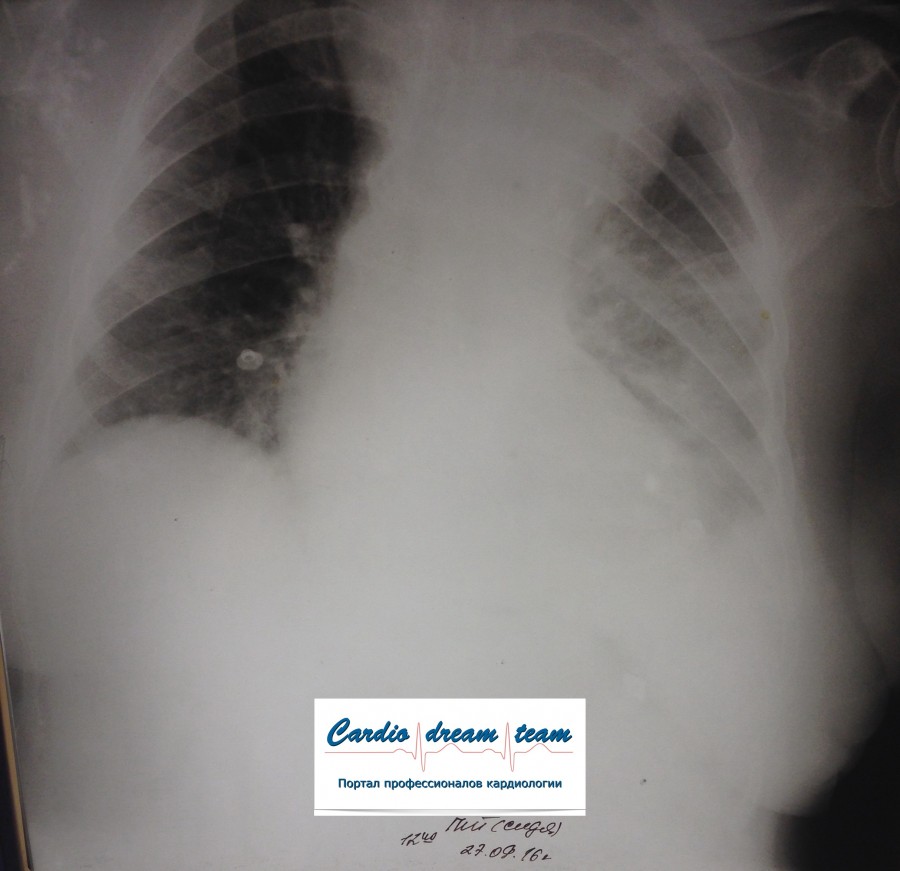

Ж 84 года. В маразме. РАА дуги и нисходящего отдела, доказана МСКТ. Поступила с болями в левом боку. На первом снимке левосторонний гемоторакс. На втором накопление жидкости до тотального уровня. На третьем после дренажа. Не оперирована. Выписана домой на 23 день госпитализации.